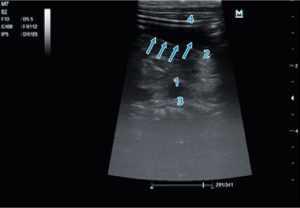

Рис. 4. Изменения эхогенности в постпилорической зоне: 1 — тело поджелудочной железы; 2 — пилорический канал с анэхогенным содержимым; 3 — селезеночная вена; 4 — паренхима печени. Проекция зонда указана стрелками — виден двойной параллельный контур

Fig. 4. Changes in echogenicity in the postpyloric zone: 1 — body of the pancreas, 2 — pyloric canal with anechoic contents, 3 — splenic vein, 4 — liver parenchyma. In the picture, the projection of the probe is indicated by arrows — a double parallel contour is visible